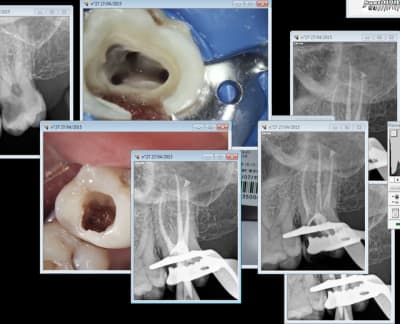

non, isthme, c'est entre les 2 canx principaux. Comme sur l'image ci jointe par ex:

> non, isthme, c'est entre les 2 canx principaux. Comme sur l'image ci jointe par

> ex: